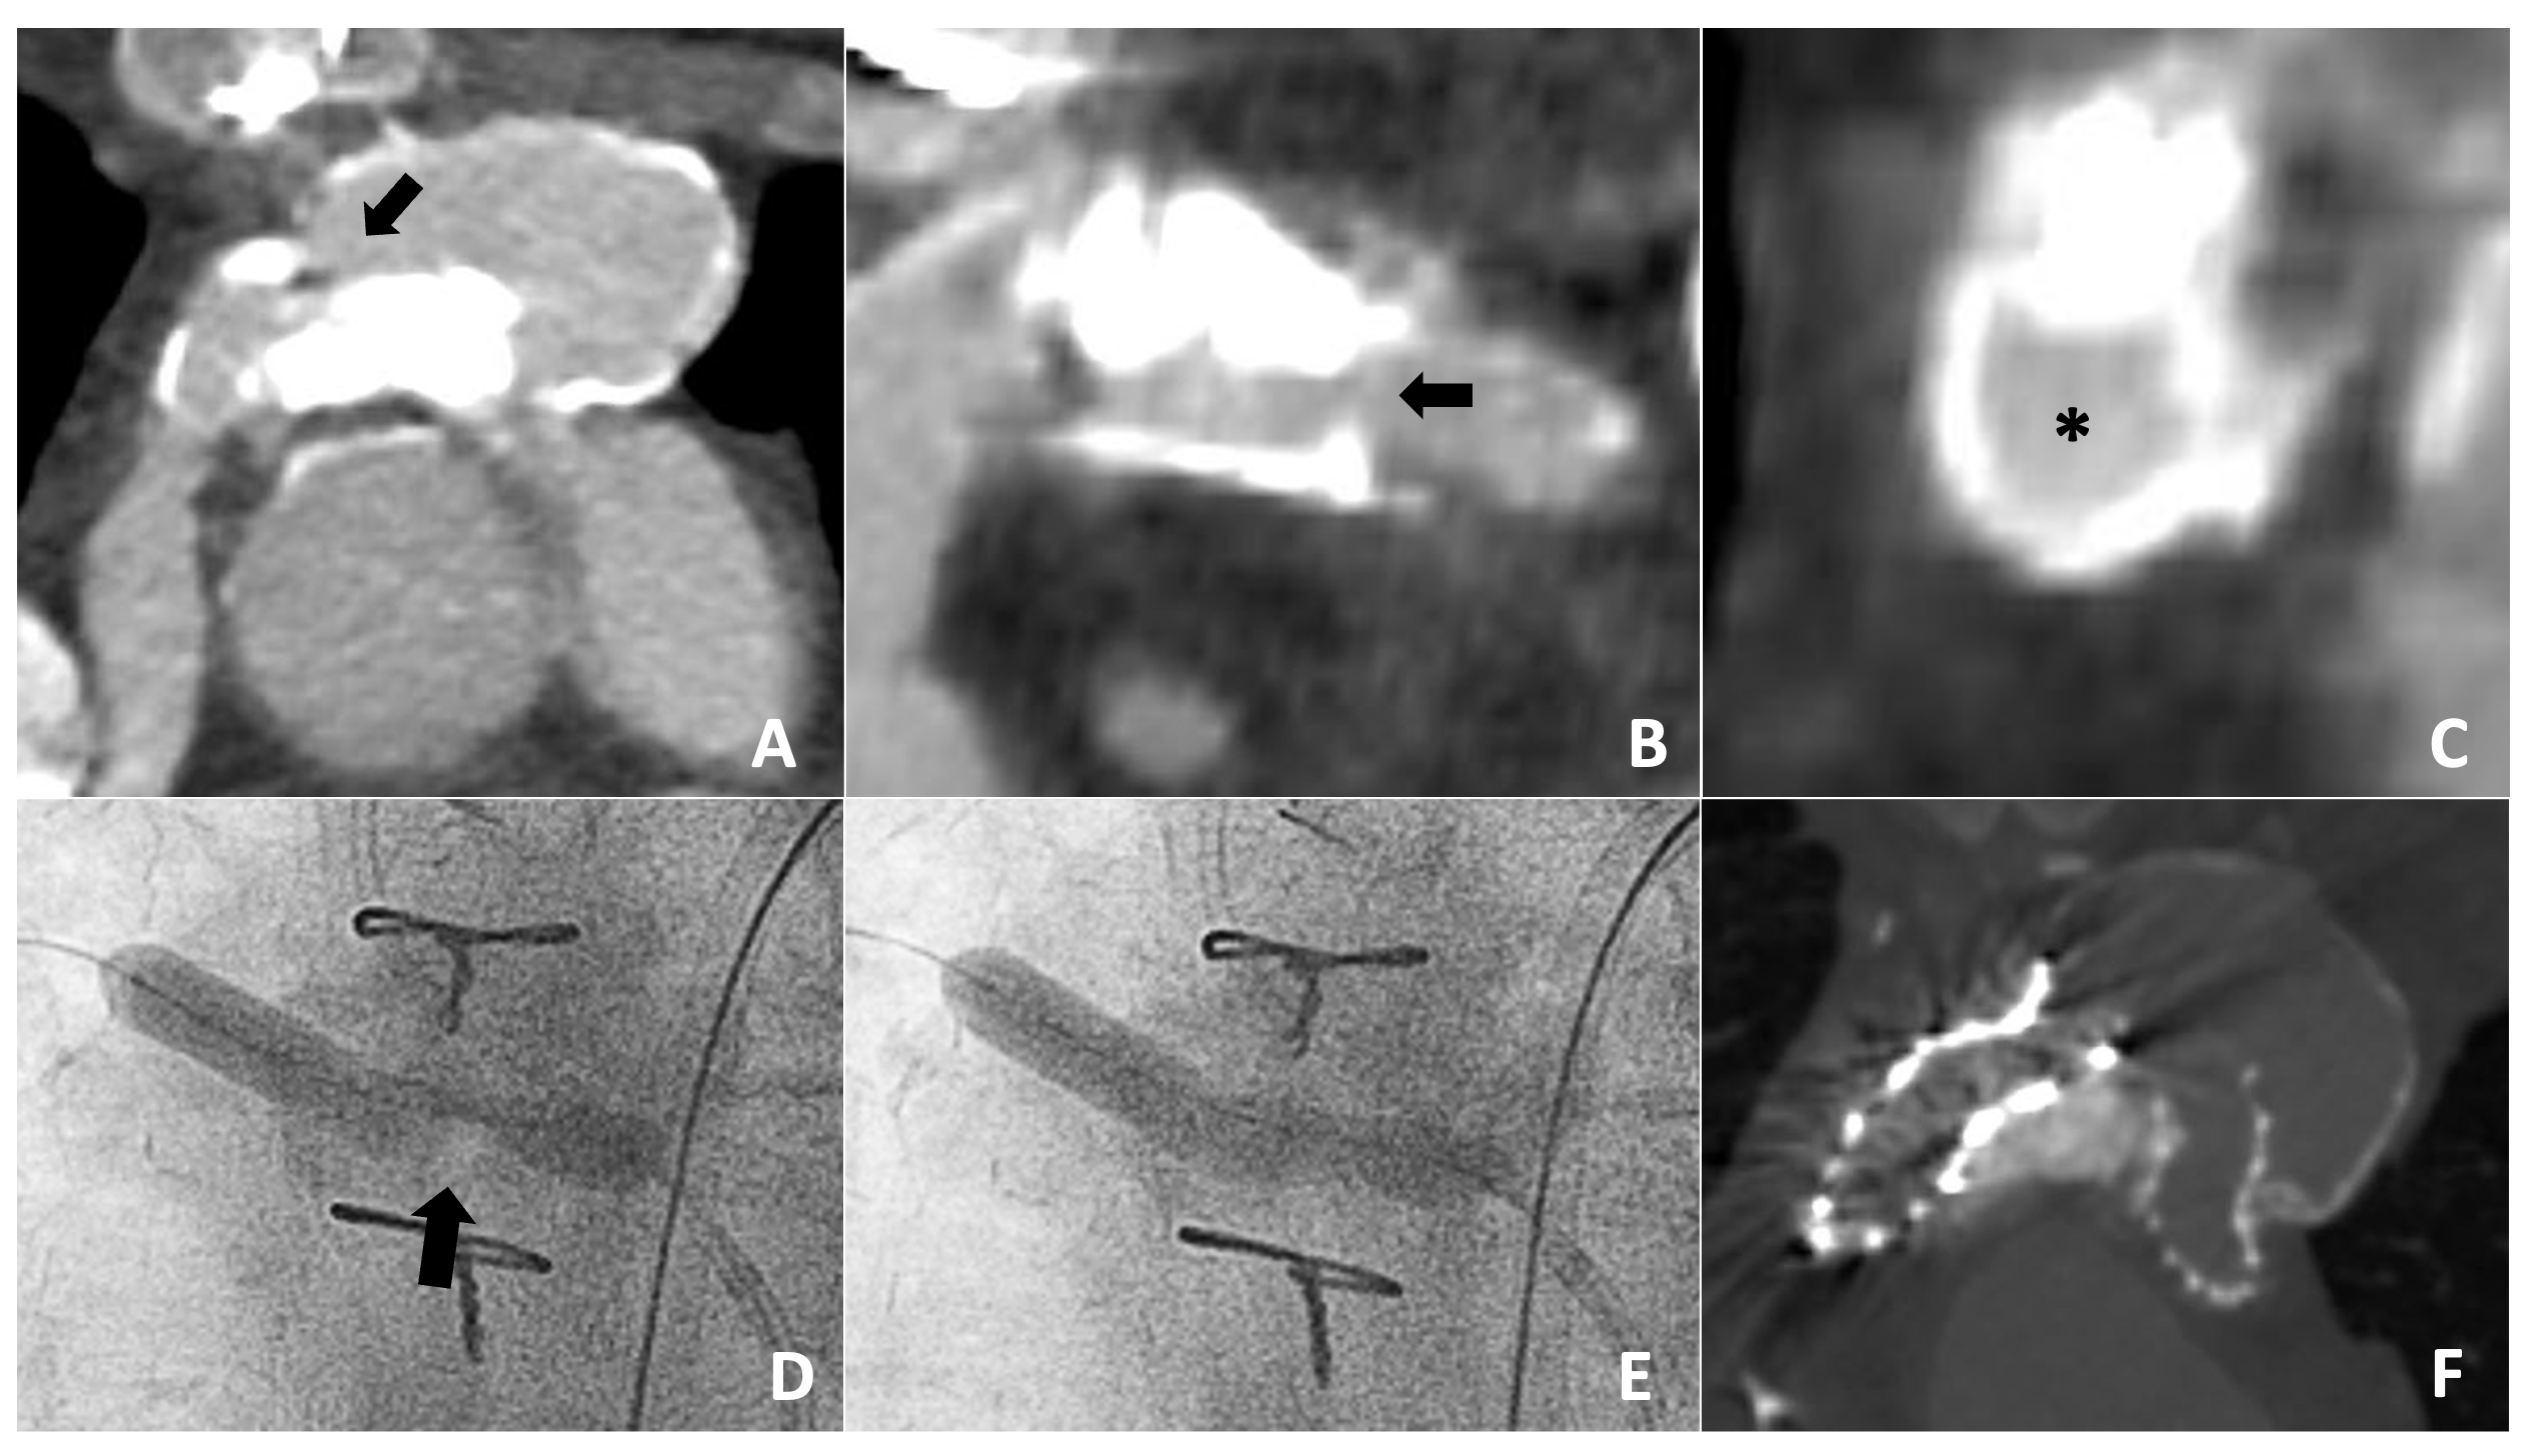

A 71-year-old man with a history of aortic coarctation and a bicuspid aortic valve status post-patch angioplasty of his aortic coarctation at age 2, patch revision at age 10, and implantation of a 16-mm ascending-to-descending aortic bypass graft at age 30. Following decades of limited cardiovascular follow-up, he presented with systolic blood pressures of 160 mm Hg, an echo derived aortic arch mean gradient of 48 mm Hg, and a CTA demonstrating a severely calcified transverse arch stenosis (< 5 mm) with severely stenotic proximal and distal bypass conduit stenoses (Figure 2A- D). The decision was made to proceed with lithotripsy-assisted native coarctation stenting.

A 12 x 30-mm Shockwave lithotripsy balloon was advanced over an 0.018-inch wire, inflated to 3 atm within the coarcted segment under rapid pacing conditions, and 30 consecutive lithotripsy pulses were delivered prior to balloon deflation. This process was repeated 9 times for a total delivery of 300 pulses. A 3.4-cm covered CCPS was advanced over a 0.035-inch wire and deployed within the coarctation over a 14-mm balloon at 6 atm. Stent post-dilation carried out with a 12-mm non-compliant balloon to 8 atm, intentionally leaving a mild mid-stent waist to avoid aortic wall injury. A 20-mm Z-MED balloon (B. Braun) was advanced into the stent and inflated to 5 atm, solely intending to flare the proximal stent to improve aortic wall apposition; however, at low pressure, the minimum diameter of the CCPS expanded to from 12 to 15 mm. Stent strut jailbreaking of the covered left subclavian artery was performed and the procedure was concluded. Final angiography showed no evidence of aortic wall injury, and the arch gradient was reduced from 42 mm Hg to 4 mm Hg (Figure 2E and F). There were no procedural complications, and the patient was discharged the following day.